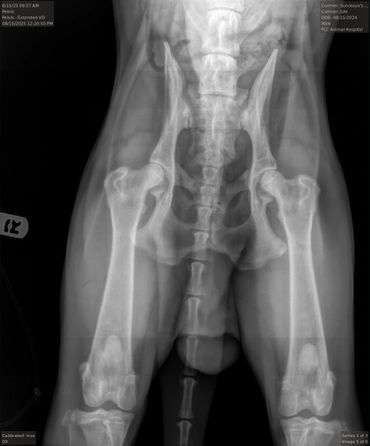

Hips (SV): Normal

HD Breeding Value (SV): 83

PennHIP: L: 0.4, R: 0.42